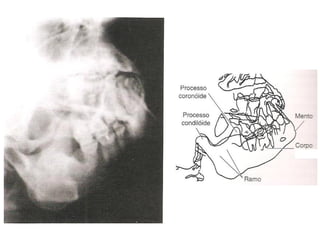

Radiografia do crânio

• Estruturas internas são mais estudadas com aquisições de

imagens mais detalhadas.

Alterações visualizadas:

Fraturas;

Neoplasias;

Inflamações;

Distúrbios articulares (ATM);

Lesões por PAF;

Adenomas hipofisários;

Mieloma múltiplo;

Doença de Paget (osteíte deformante).

Mandíbula

Ramo da

Côndilo da mandíbula